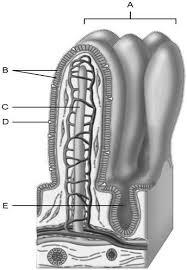

Continuation of the mesentery

D

Absorptive cells that line the intestinal tract

B

Cell type specialized to secrete mucus into the lumen of the intestinal tract.

D

Wide lymph capillary located in the villus.

C

Paneth cells are found here.

E